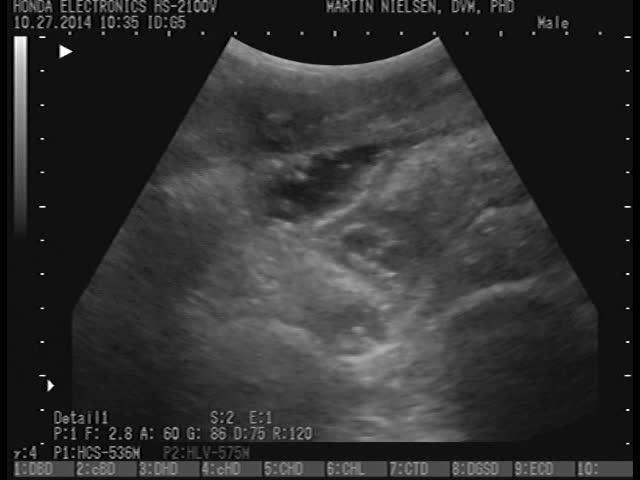

Ascarid parasites visualized within small intestinal loops by transabdominal ultrasonography in a naturally infected foal.